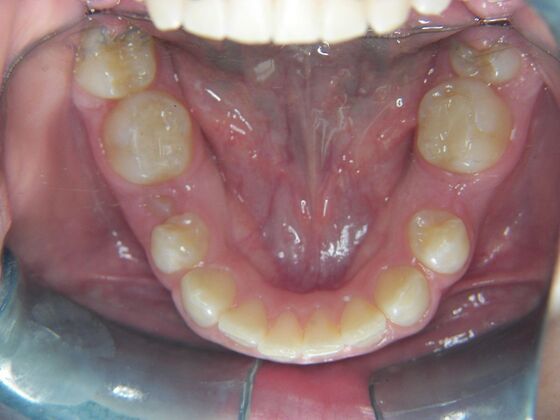

Patient is 9 years old and presents with 100% overbite and blocked out upper and lower lateral incisors. Both upper central incisors are palatally inclined causing a lack of space available for most anterior teeth. Advised her parents that she needs Phase I Interceptive Orthodontic treatment to provide room for all upper and lower front teeth. Phase I treatment was begun and finished, then began Phase II treatment shortly thereafter to finalize case. Removable retainer were fabricated for retention.